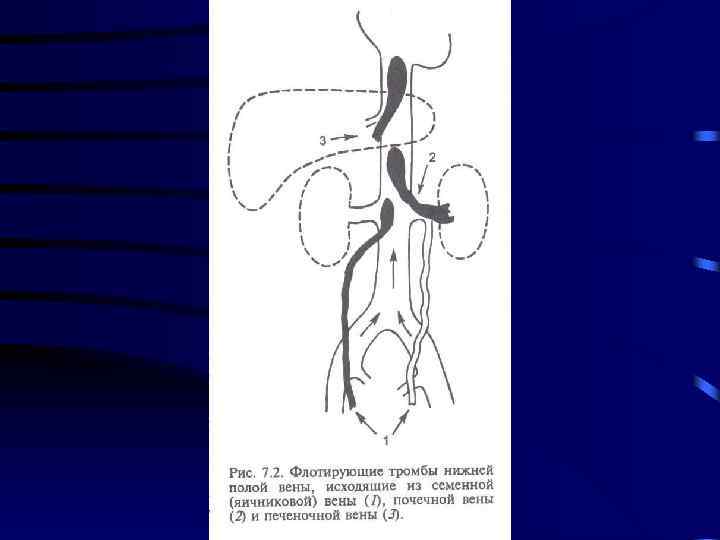

Лечение: 1. Консервативная терапия: a) Эластическое бинтование с возвышенным положением b) Гепарин c) Антибиотики d) Покой 5 -7 суток 2. При флотирующем или эмбологенном тромбозе хирургическое лечение: a) Установка Кава-Фильтра b) Пликация вен выше места тромба